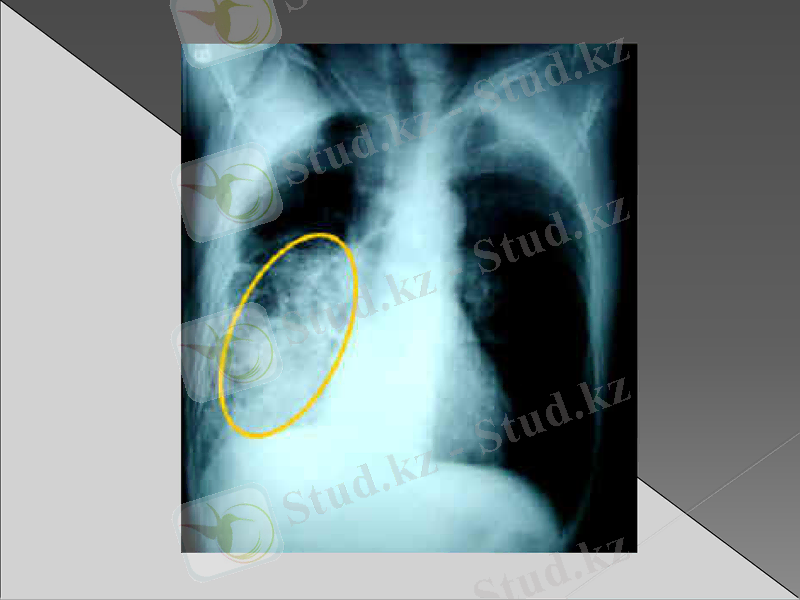

Рентгенография : инфильтрация немесе қараю зоналары (пневмонияның түріне байланысты өкпе тінінің зақымдалуы)

Рентгендік зерттеуде бірінші күні айқын көрінетін инфильтрациялық өзгерістер болмайды. Бұл кезде әрең байқалатын вуаль тәрізді нәзік көлеңкелену болуы мүмкін. Оның интенсивтілі біртіндеп күшейіп нағыз шыңына 5- тәулікте жетеді. Қан анализінде лейкоцитоз 15-30х 10/л дейін көбейеді. Лейко формулада нейтрофилдердің жетілмеген жас түрі көбейеді. ЭТЖ жоғарылайды. Сонымен бірге қанда қабынудың биохимиялық белгілері анықталады. Альфа және гамма глобулиндердің, фибриногеннің жоғарылауы, С реактивті белоктің пайда болуы. Қақырықта белоктің, фибриннің, эритроциттердің, лейкоциттердің мөлшері көп. Қақырық жағындысында қоздырғыш табылады.